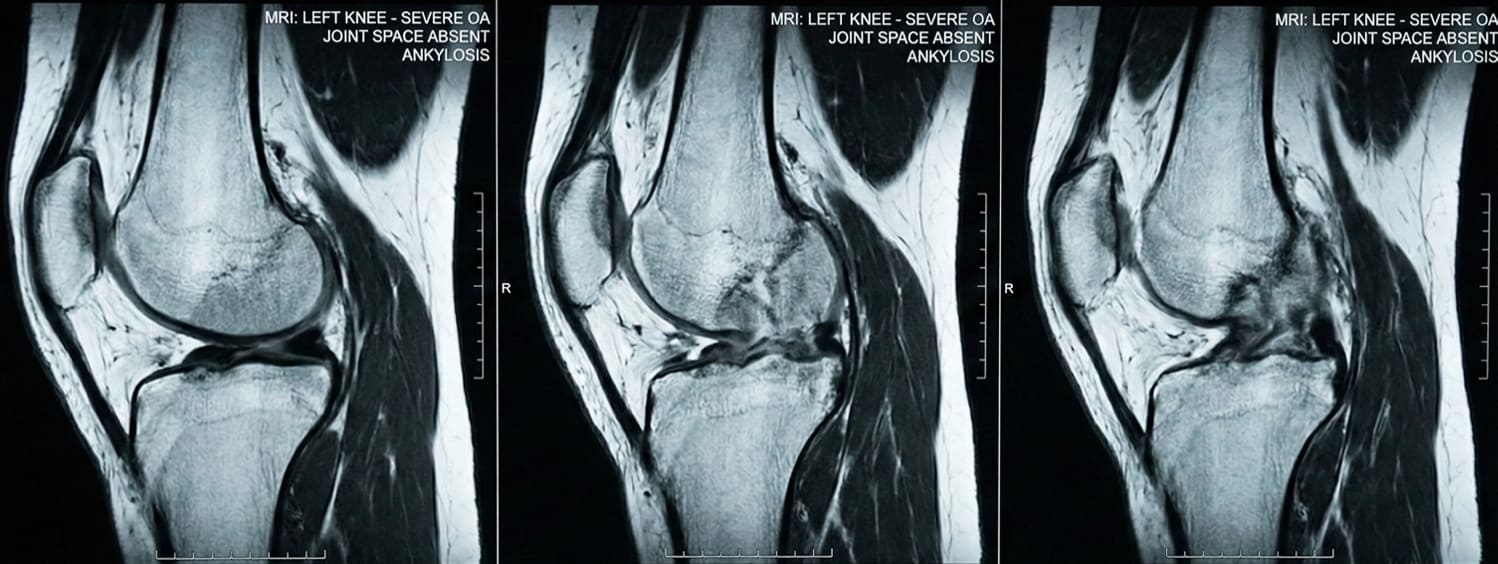

Cuando veas esto en una radiografía, tu articulación ya no podrá recuperarse.

Resonancia magnética: el espacio articular ha desaparecido por completo.

Una realidad que ya no se puede corregir.

Lo que el médico verá en la imagen:

ESPACIO ARTICULAR COMPLETAMENTE AUSENTE

El hueso roza contra el hueso.